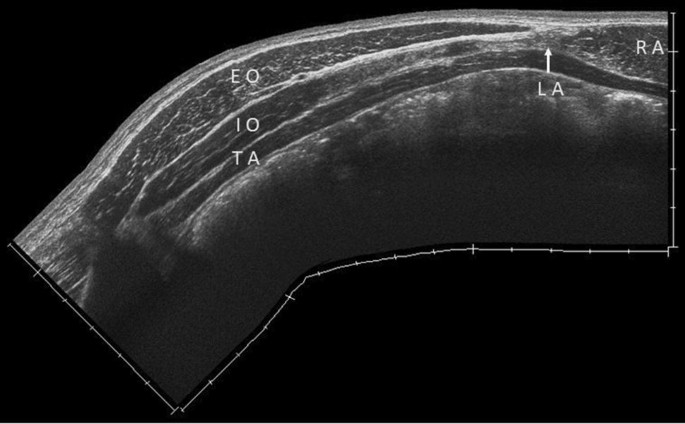

50+ Abdominal Vascular Anatomy Ultrasound. Introduction to sonographic abdominal anatomy. Abdominal ultrasonography (also called abdominal ultrasound imaging or abdominal sonography) is a form of medical ultrasonography (medical application of ultrasound technology) to visualise abdominal anatomical structures.

An increase in diameter of 50% greater than original artery. Some anatomy ultrasounds will be performed on machines with video recording capabilities. 1 abdominal vascular ultrasound renal duplex sonography 40 vascular anatomy right renal artery arises anterolateral from the aorta left renal artery usually lateral or posterolateral rra passes posterior to. Learn about vascular ultrasound arterial anatomy with free interactive flashcards.